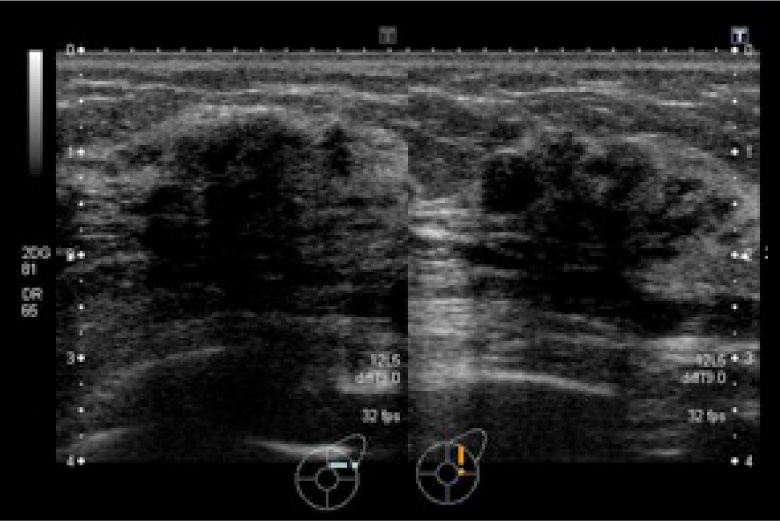

超音波検査

音の性質を利用して生体内の血流状態、及び断層像を描出することができます。腹部、頚部、乳腺、甲状腺、唾液腺などの実質臓器や胃・大腸などの消化管を見ています。無侵襲で痛みはほとんどなく被ばくが有りませんので安心して検査をお受けください。また乳腺領域の検査は女性技師が対応致します。

LOGIQ E9

乳腺腫瘍

肝臓腫瘍